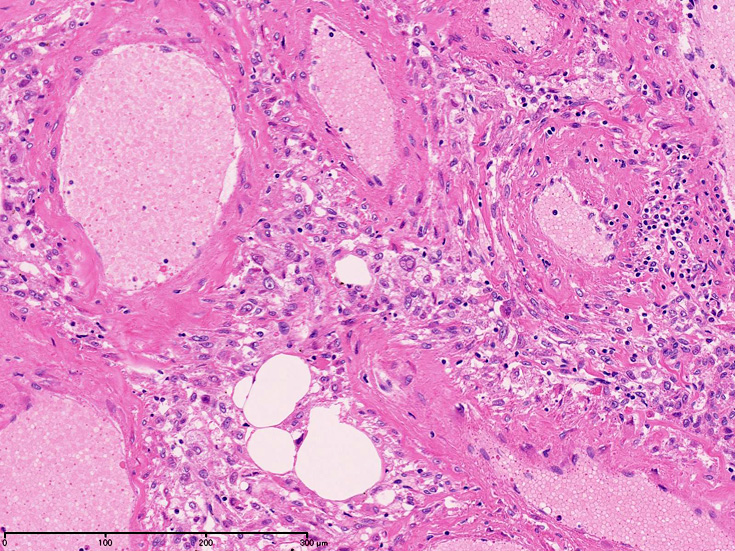

顕微鏡で平滑筋だけにより構成される, 広い部分が認められ、核腫大, hyperchormasia,少数の核分裂像が出現することがある。細胞質内顆粒が見られることがある。

かなり大きな部分で未熟な平滑筋あるいはmyoblast増殖を認めることがある。核は類円形で細胞質は淡明である。細胞は中心の細動脈に対してpalisade構造をとる。

- 血管は特徴的な構成成分でとても厚く異常な壁をもつ。多くの領域で血管の筋組織は厚い線維結合組織で置換され厚みは不規則となりArteriovenous malformationに認められる動脈化静脈に類似する。内弾性板は通常欠損しているか存在しても断片化, 複層化しボロボロである。

- AMLomaの血管は蛇行し壁が部分的にひ薄化拡張して, 小型の静脈瘤様動脈瘤を形成している。